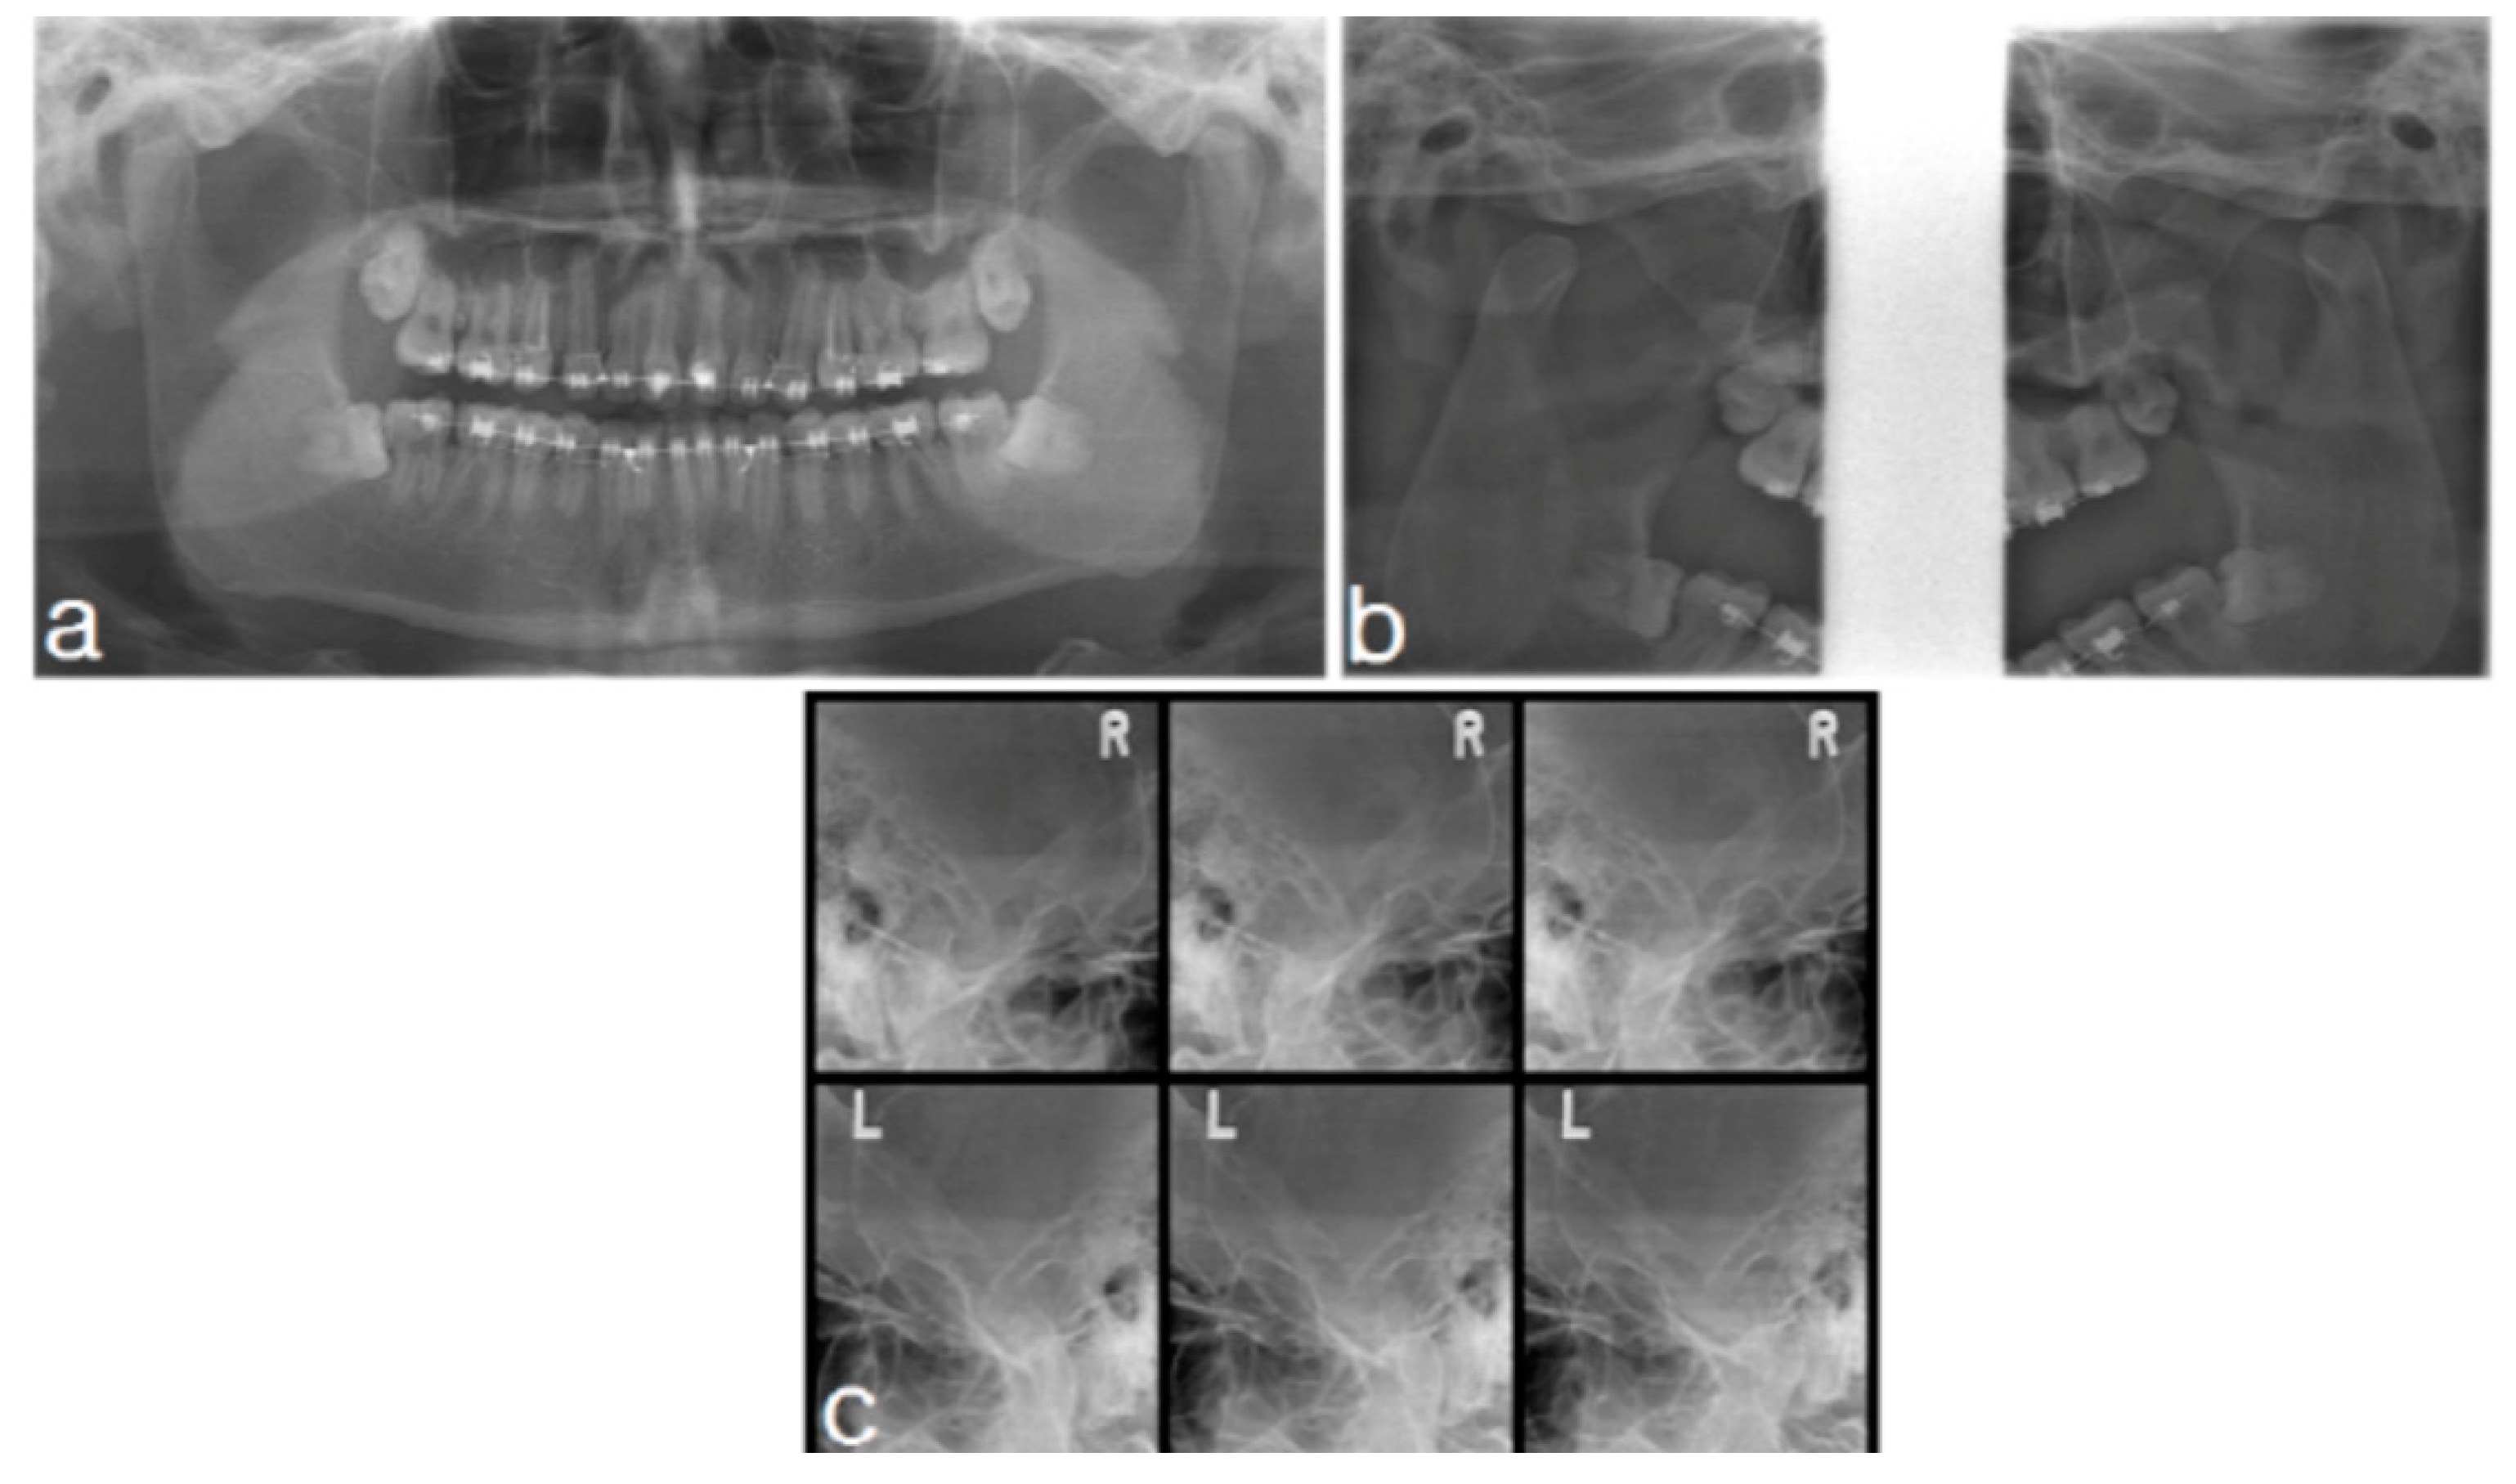

2.2.2. Imaging

2.2.3. Treatment